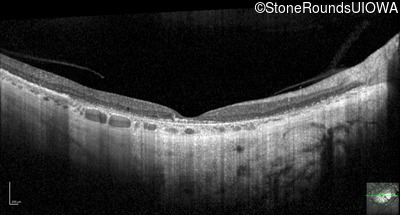

Optical Coherence Tomography - Left - 5/400

Exemplar / OCT Stack